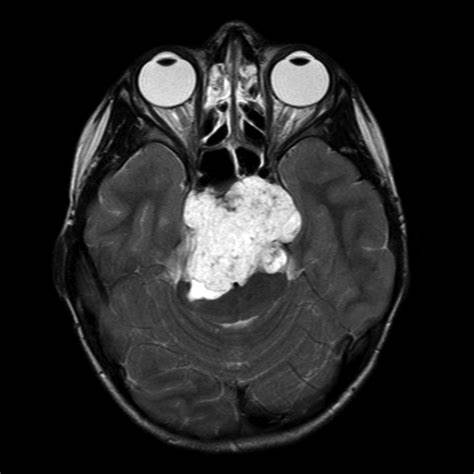

對(duì)于腦脊索瘤顯微外科手術(shù),國(guó)際顱底腫瘤手術(shù)教授巴特朗菲教授是擅長(zhǎng)的,巴特朗菲教授在術(shù)中核磁、神經(jīng)導(dǎo)航等高復(fù)雜設(shè)備的輔助下,其腦脊索瘤平均切除率達(dá)到了90%以上。在國(guó)內(nèi),一位95后小姑娘雯雯(化名)身患橋前斜坡脊索瘤,斜坡位置的脊索瘤手術(shù)難度較大,難以切除干凈,較易復(fù)發(fā)。雯雯在國(guó)內(nèi)一次手術(shù)后仍然還有很大一部分殘留,效果不理想,而國(guó)內(nèi)醫(yī)生告知二次手術(shù)風(fēng)險(xiǎn)太大,建議保守治療。后經(jīng)過(guò)INC的聯(lián)系,找到了巴特朗菲教授,巴特朗菲教授為雯雯實(shí)施了從枕下乙狀竇后入路對(duì)腦干實(shí)施廣泛解壓切除術(shù),手術(shù)很成功,手術(shù)切除率達(dá)到了95%以上。

雯雯脊索瘤影像圖